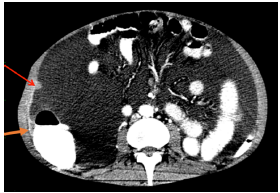

On physical examination, the patient was in poor general condition, tachycardic, normotensive, afebrile and with cachexia; his weight was 48kg, and he presented with distended abdomen with shifting dullness, cardiopulmonary auscultation without alterations, positive ascitic wave and pain on palpation without signs of peritoneal irritation, and peritoneal dialysis catheter without local inflammatory signs. A computed tomography (CT) of the abdomen was performed, showing a single nodular image of well-defined edges, with soft tissue density, of 12mm in diameter, located in the peritoneal plane of the right abdominal wall and associated with abundant ascites of free characteristics, splenomegaly and slight thickening of the parietal peritoneum (Figure 1 and 2).

CT scan of the abdomen, axial plane, showing thickening (orange arrow) and nodular lesion (red arrow) in the parietal peritoneum.

Figure 2: CT scan of the abdomen, axial plane, showing thickening (orange arrow) and nodular lesion (red arrow) in the parietal peritoneum.

Source: Document obtained during the study.

In diagnostic imaging, PH is characterized by diffuse nodular thickening of peritoneal surfaces that have soft tissue attenuation on CT and are enhanced by intravenous contrast administration. Other findings may include ascites, hepatic or splenic microabscesses of miliary distribution, peritoneal or hepatic granulomas, and diffuse striation of the omentum or mesenteric fat. 12,13

Finding disseminated peritoneal lymph-adenopathies or nodules is highly relevant as they suggest peritoneal involvement secondary to hematogenous dissemination. 13 Gastrointestinal involvement (thickening of the terminal or blind ileum) by histoplasmosis suggests dissemination by contiguity secondary to intestinal microperforations. PH is included in the spectrum of granulomatous peritonitis and, therefore, its imaging characteristics are indistinguishable from peritoneal tuberculosis infection. 12